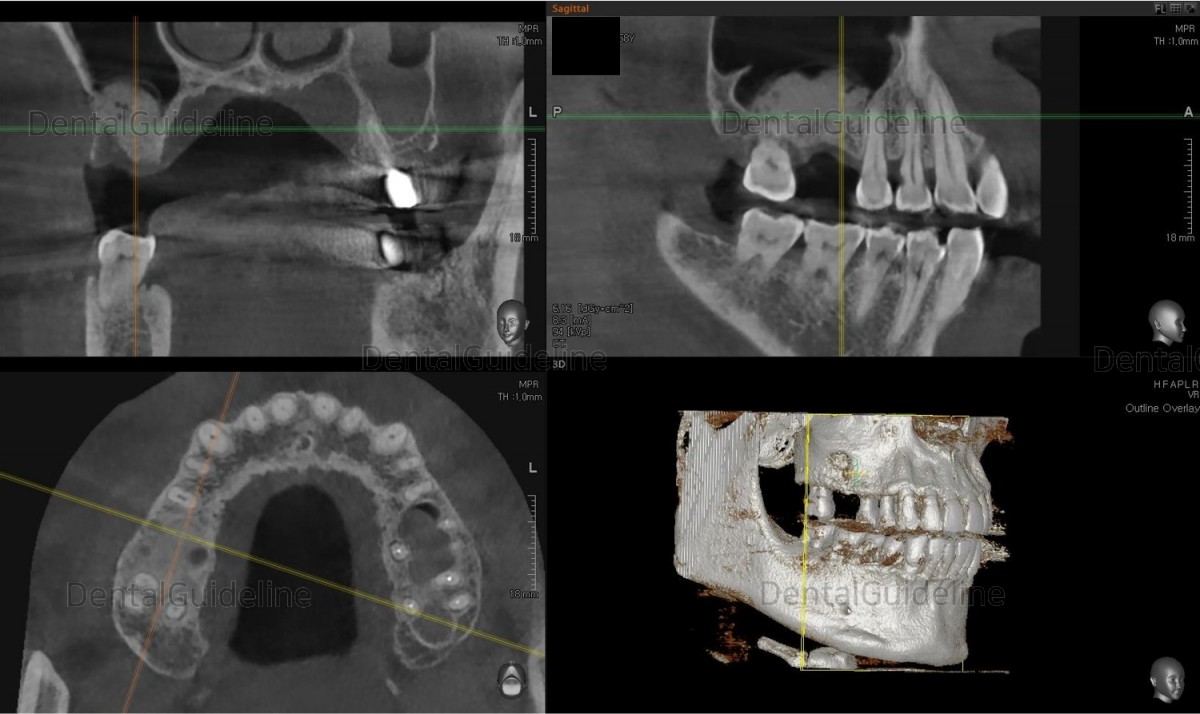

18. The same day CBCT scan.